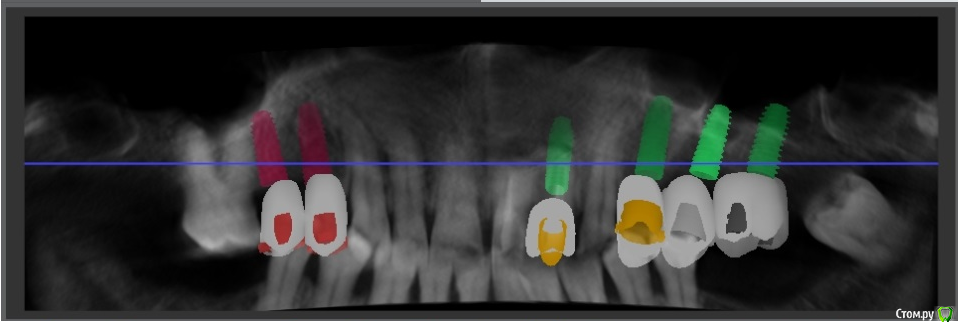

Доктор Хаус Опубликовано 9 апреля, 2016 Поделиться Опубликовано 9 апреля, 2016 Здорова Роберт, а постановку делал ? Совмещал виртуальную модель с постановкой имплантов на кт? То же есть впечатление что медиально наклонил. Ссылка на комментарий

Robinbobin Опубликовано 11 апреля, 2016 Автор Поделиться Опубликовано 11 апреля, 2016 (изменено) Здорова Роберт, а постановку делал ? Совмещал виртуальную модель с постановкой имплантов на кт? То же есть впечатление что медиально наклонил. привет Изменено 11 апреля, 2016 пользователем Robinbobin Ссылка на комментарий